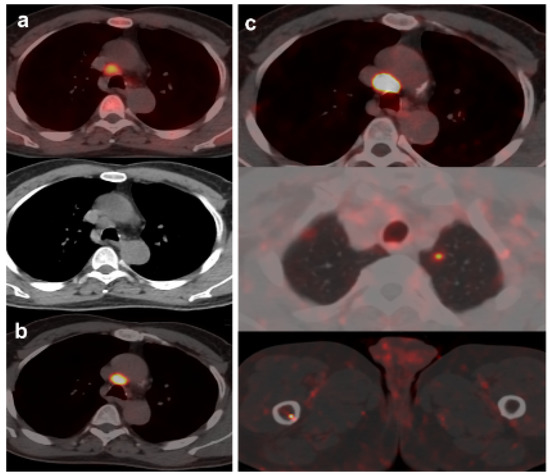

Derived from positive [18F]DCFPyL-PET/CT, 19 patients underwent additional diagnostic procedures to confirm the results: 8 by imaging (3/8 was confirmed) and 11 by histological analysis (8/11 was confirmed) (Figure 3 and Figure 4).

Figure 4.

70-year-old patient. Gleason 9 PCa, treated initially with RP and radiotherapy after his first BCR. Second BCR (PSA 0.7 ng/mL, PSAdt 5.6 months, PSAvel 0.05 ng/mL/month) with [18F]F-choline (a) and [18F]DCFPyL scans showing mediastinal lymph node tracer uptake (b) reported as inflammatory process. Follow-up was decided and PSA level continued increasing. A new [18F]DCFPyL scan (c) was performed 3 months later, showing an increase in size and metabolism of mediastinal lymph node with additional microfoci of radiotracer uptake in lung and bone, suspicious of metastases. An endobronchial ultrasound-guided lymph node biopsy confirmed prostatic origin of metastasis. ADT + Apalutamide was initiated (escalation).